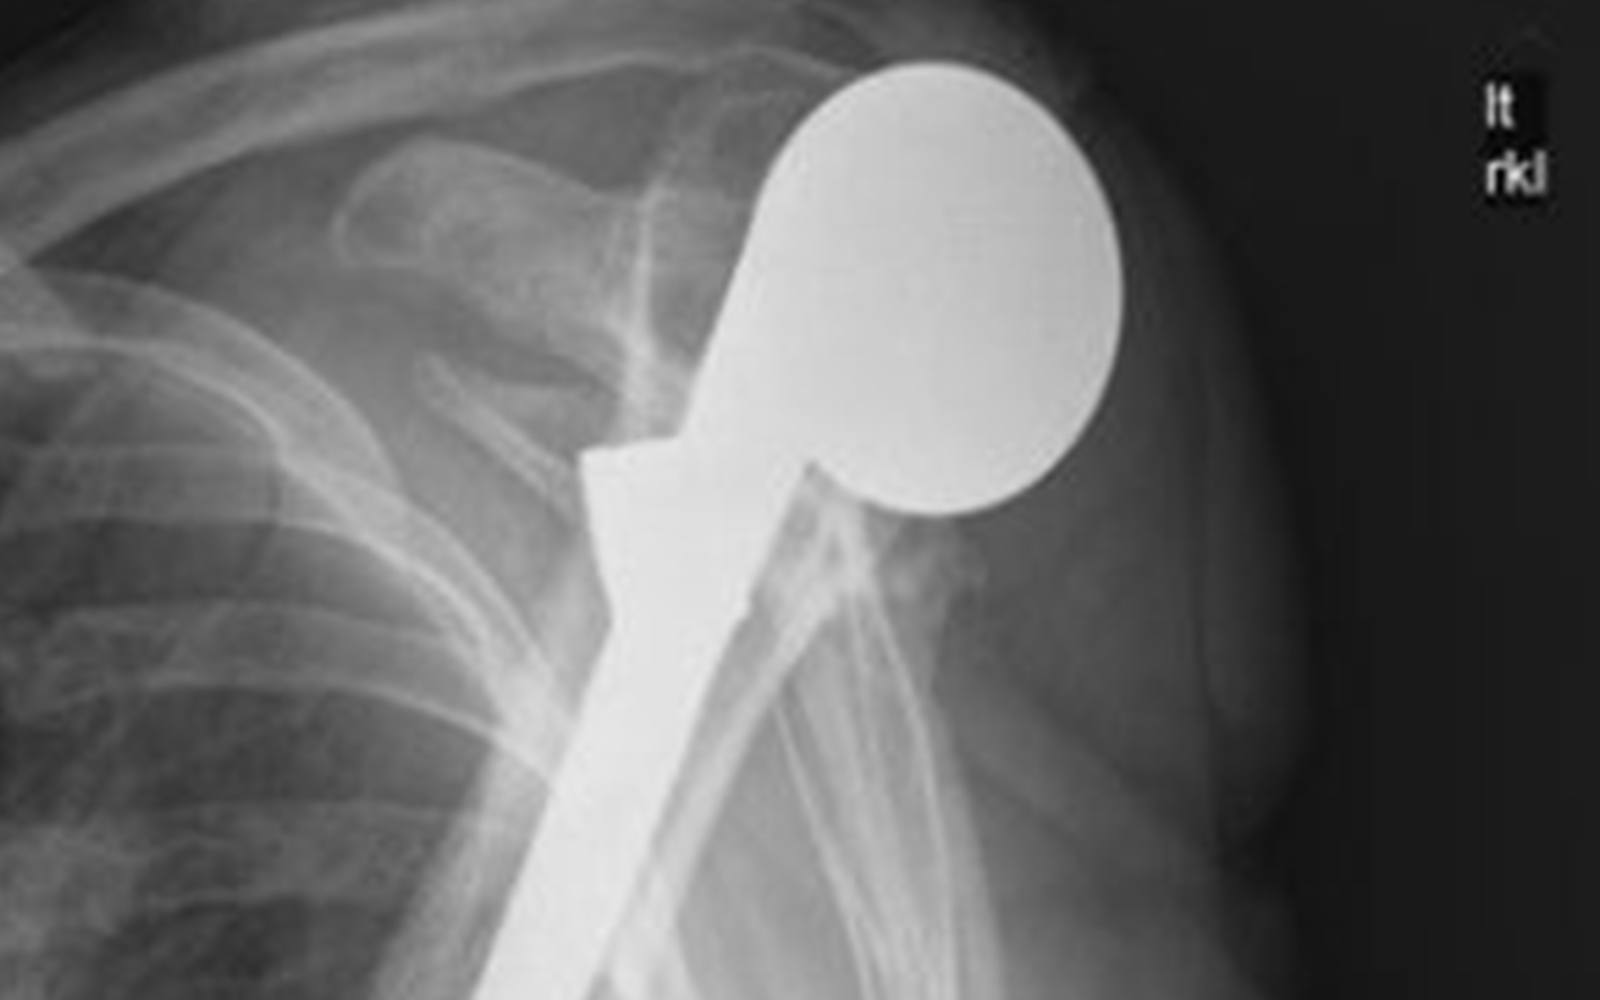

Instability Remains a Leading Cause of Complications in Reverse Shoulder Arthroplasty

Moby Parsons, MD